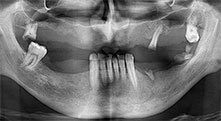

Bratu: We routinely use the instruments for harvesting bone blocks and splitting alveolar ridges. We also use the Piezomed B6/B7 for osteotomy of impacted teeth and removing failed implants. All indications that require deep, clean cuts.

Could you describe briefly, for example, your procedure for mobilizing bone blocks for transplantation?

Bratu: We prefer to harvest bone from the external oblique ridge of the posterior mandible, not from the interforaminal region. After the soft-tissue incision, we use the new saws to define the amount of bone to harvest. With this approach, we also use them for the entire preparation in almost 80% of cases. We may also use other piezo instruments and then at the end a chisel to mobilize the block. We find that this is a very effective surgical technique.